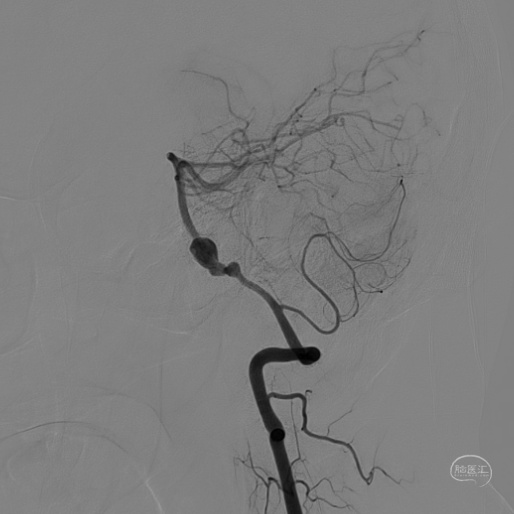

DSA:

3D重建显示基底动脉下部、双椎结合部、左椎多发夹层动脉瘤:

术后造影显示动脉瘤内造影剂滞留明显,载瘤动脉通畅。